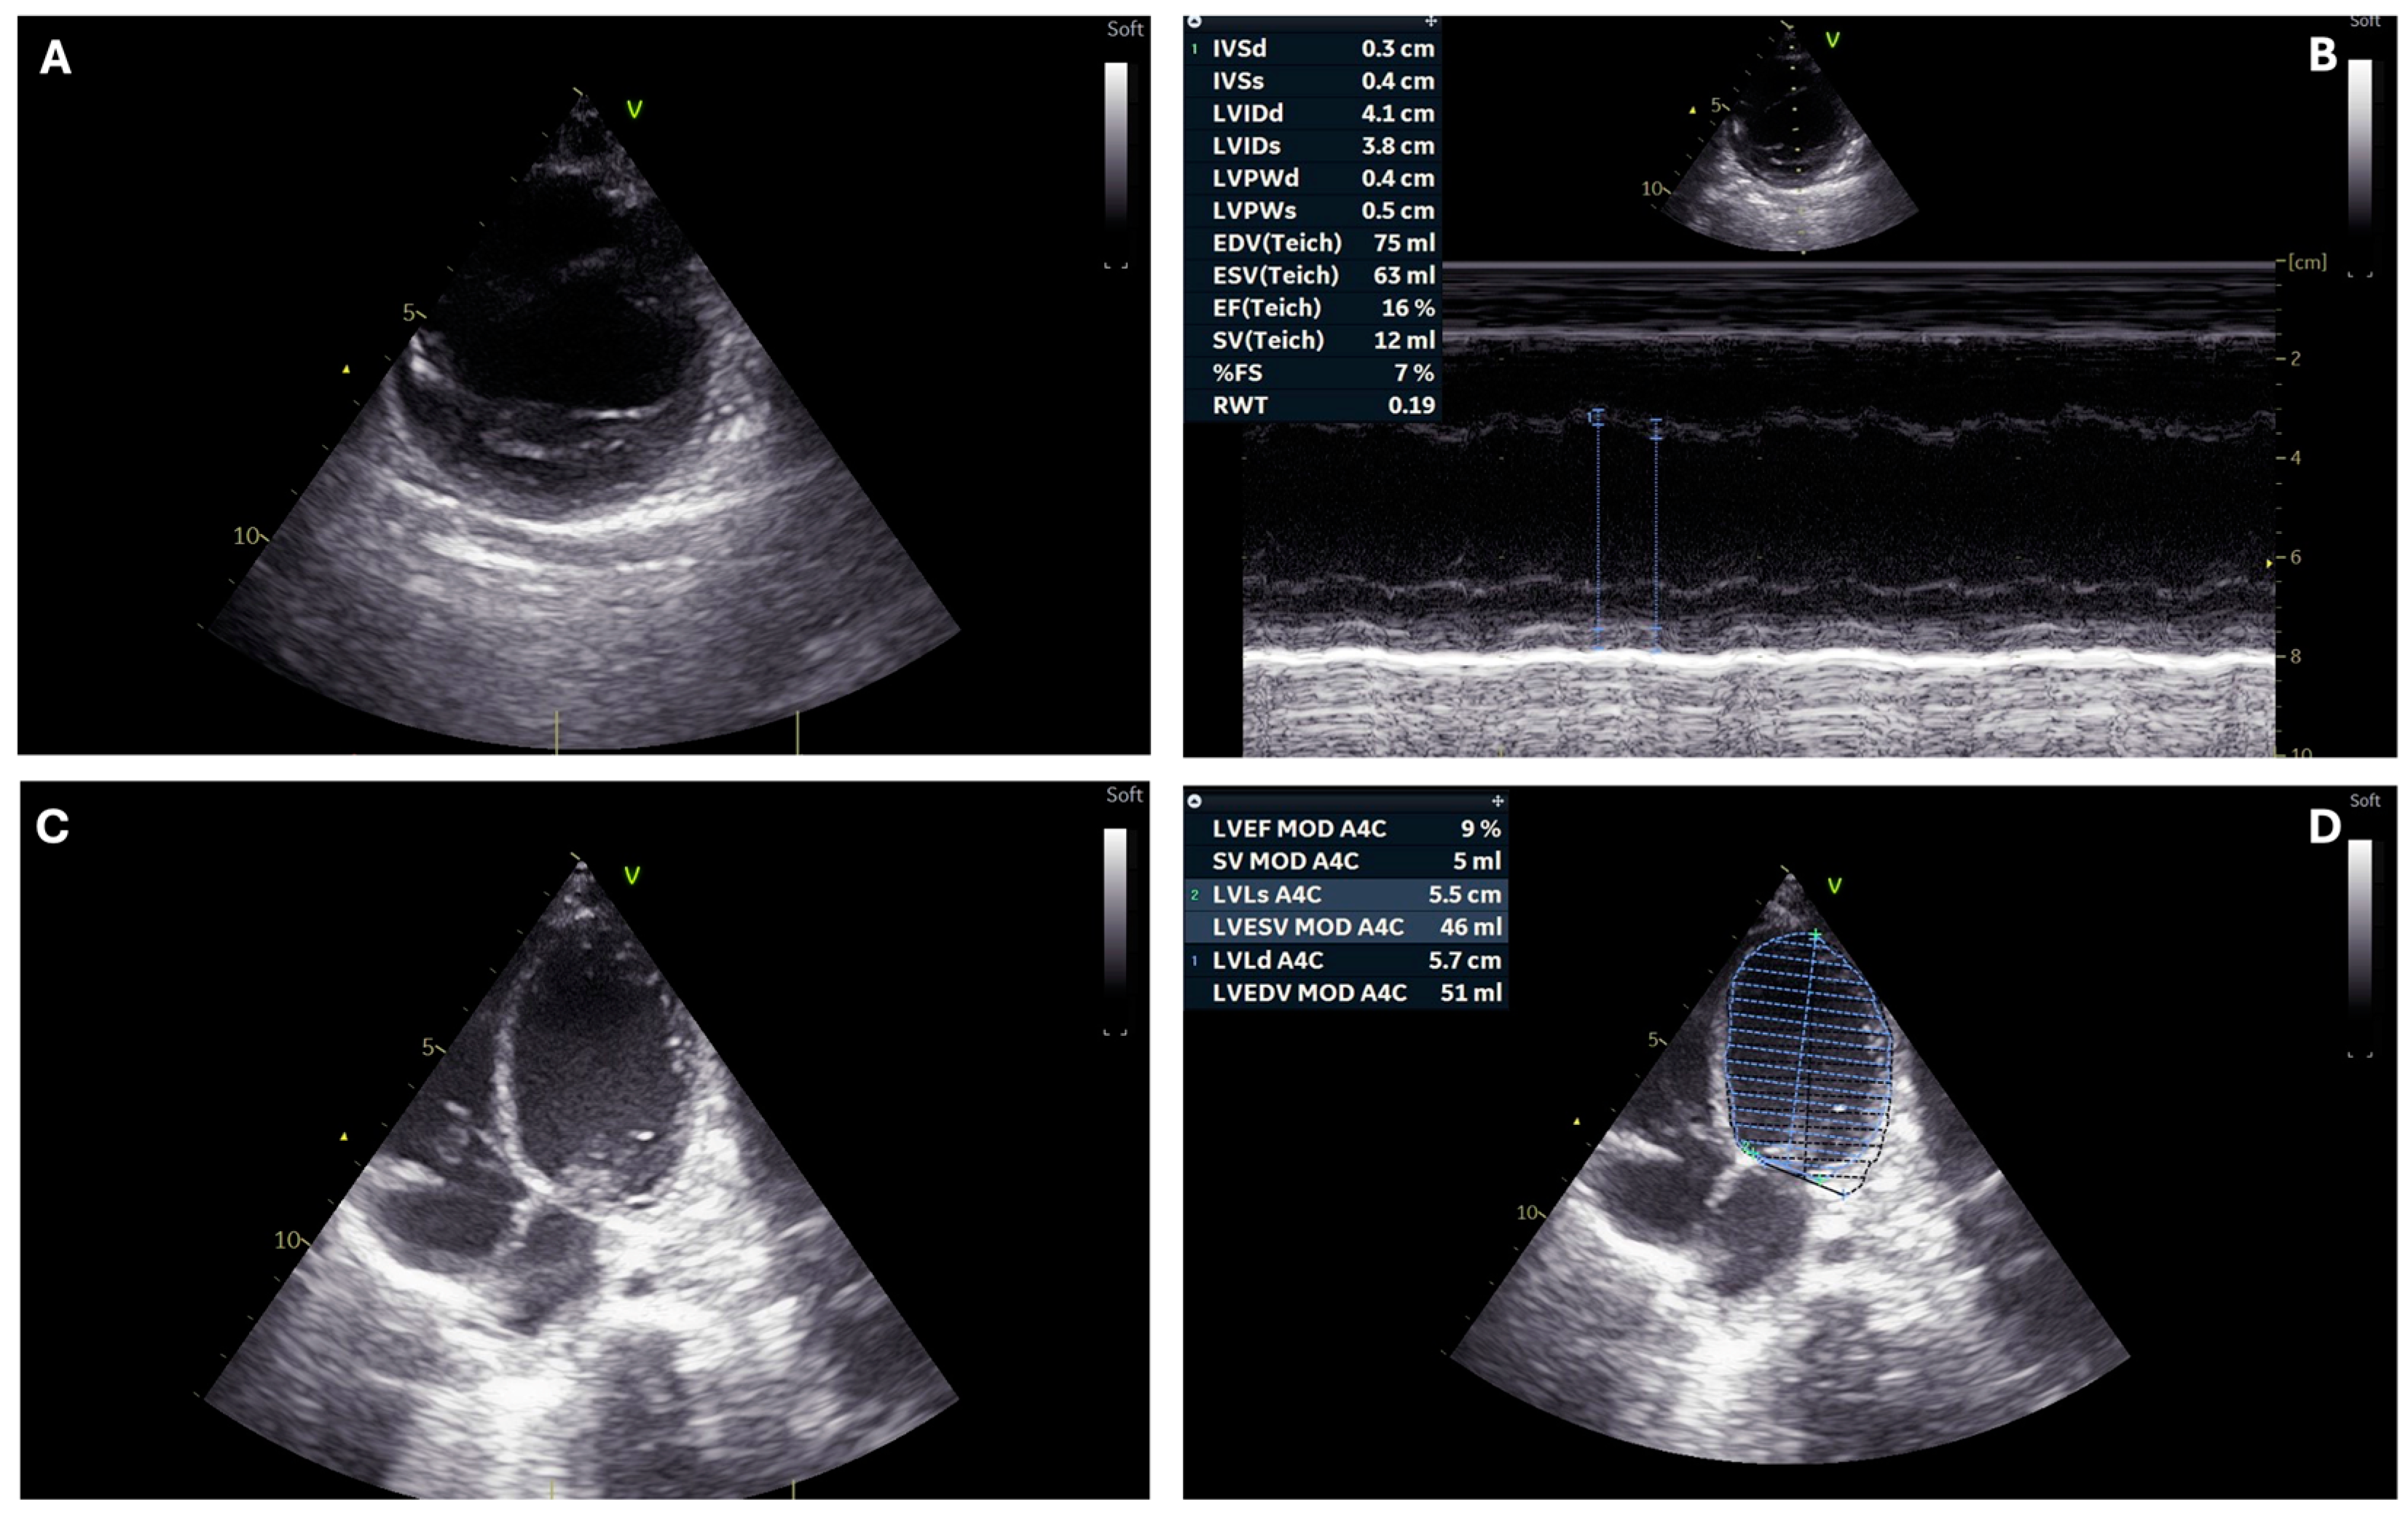

| Ventricular ejection fraction (%) | <10 | 25 | 10–15 | 10–15 | 33–35 | 10–15 |